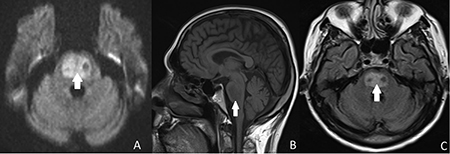

Diagnosis is confirmed on brain magnetic resonance imaging, which shows typical lesions in the pons, thalamus, or other areas of white matter.[Figure caption and citation for the preceding image starts]: Brain magnetic resonance imaging of a patient with central pontine myelinolysis showing: (a) trident-shaped hyperintensity within the pons; (b) hypointensity within the basis pontis; and (c) hyperintense focus in the central ponsBMJ Case Reports 2013; doi:10.1136/bcr-2013-009970 [Citation ends].